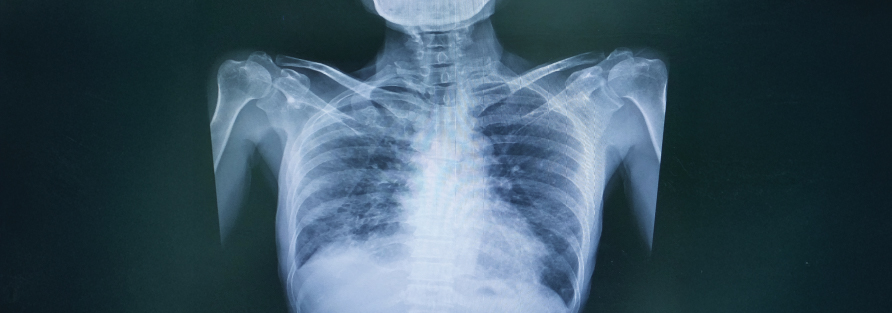

X-Ray

Our hospital's modern X-ray facility represents a significant advancement over traditional units. It's designed to produce exceptionally

clear images, ensuring accurate diagnoses. Moreover, these images can be stored in digital format,

facilitating easy access and sharing for comprehensive patient care.